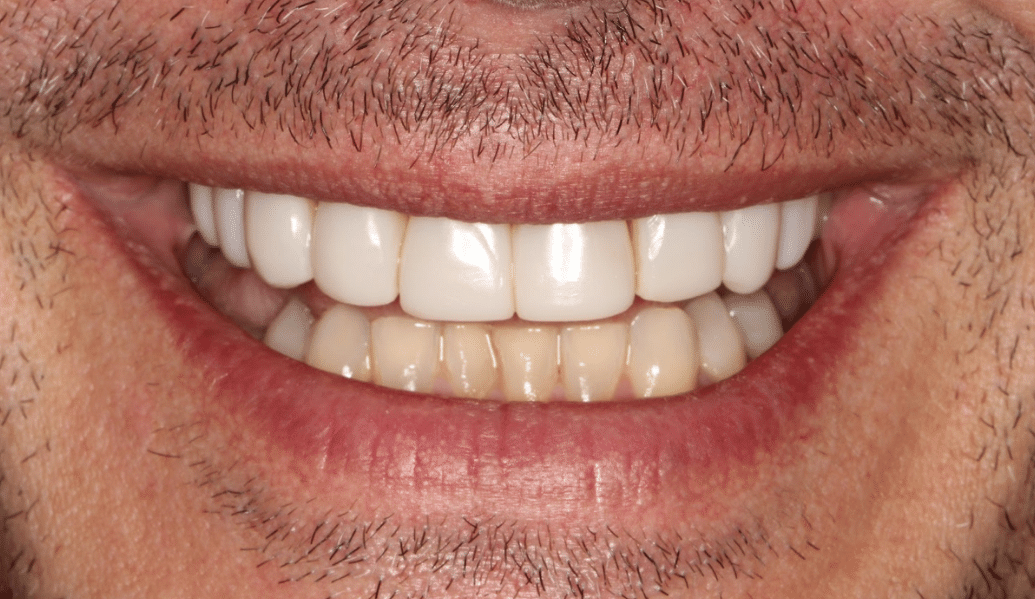

learn moreDelivering life-changing smiles and ensuring excellent dental health.

learn moreDental implants and us – together we can recreate a naturally beautiful smile.